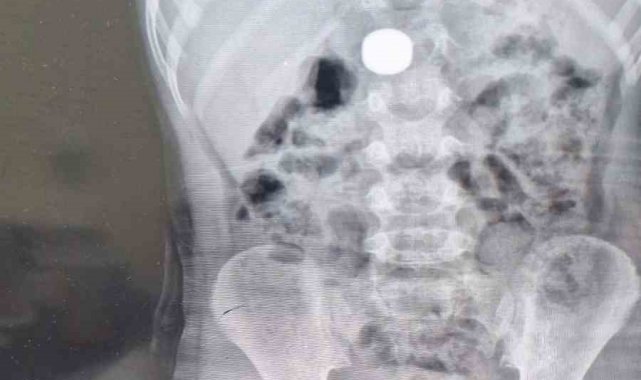

Karaman'da 4 yaşındaki İ.K.'nin mıknatıs yuttuğundan şüphelenen ailesi, Karaman Eğitim ve Araştırma Hastanesi Acil Servisi'ne başvurdu. Yapılan tetkiklerde çocuğun ince bağırsağında iki adet mıknatıs bulunduğu tespit edildi. Gözlem altına alınan çocuğun sağlık durumu 5 gün boyunca takip edildi. Çocuk Cerrahisi Uzmanı Doç. Dr. Mehmet Uysal'ın gerçekleştirdiği operasyonla bağırsakta tıkanıklığa yol açan iki mıknatıs başarılı bir şekilde çıkarıldı.

Hastayı 5 gün boyunca takibe aldıklarını belirten Doç. Dr. Mehmet Uysal, gözetim süresince çekilen filmlerde mıknatısların yer değiştirmediğini söyledi. Uysal, "Hastayı genel anestezi altında ameliyata aldık. İnce bağırsakta iki mıknatısın birbirine yapışık halde olduğunu gördük. Gerçekleştirdiğimiz operasyonla mıknatısları çıkardık. Ameliyat sonrası hastamız üçüncü gününde taburcu edildi. Şu an genel durumu iyi" dedi.